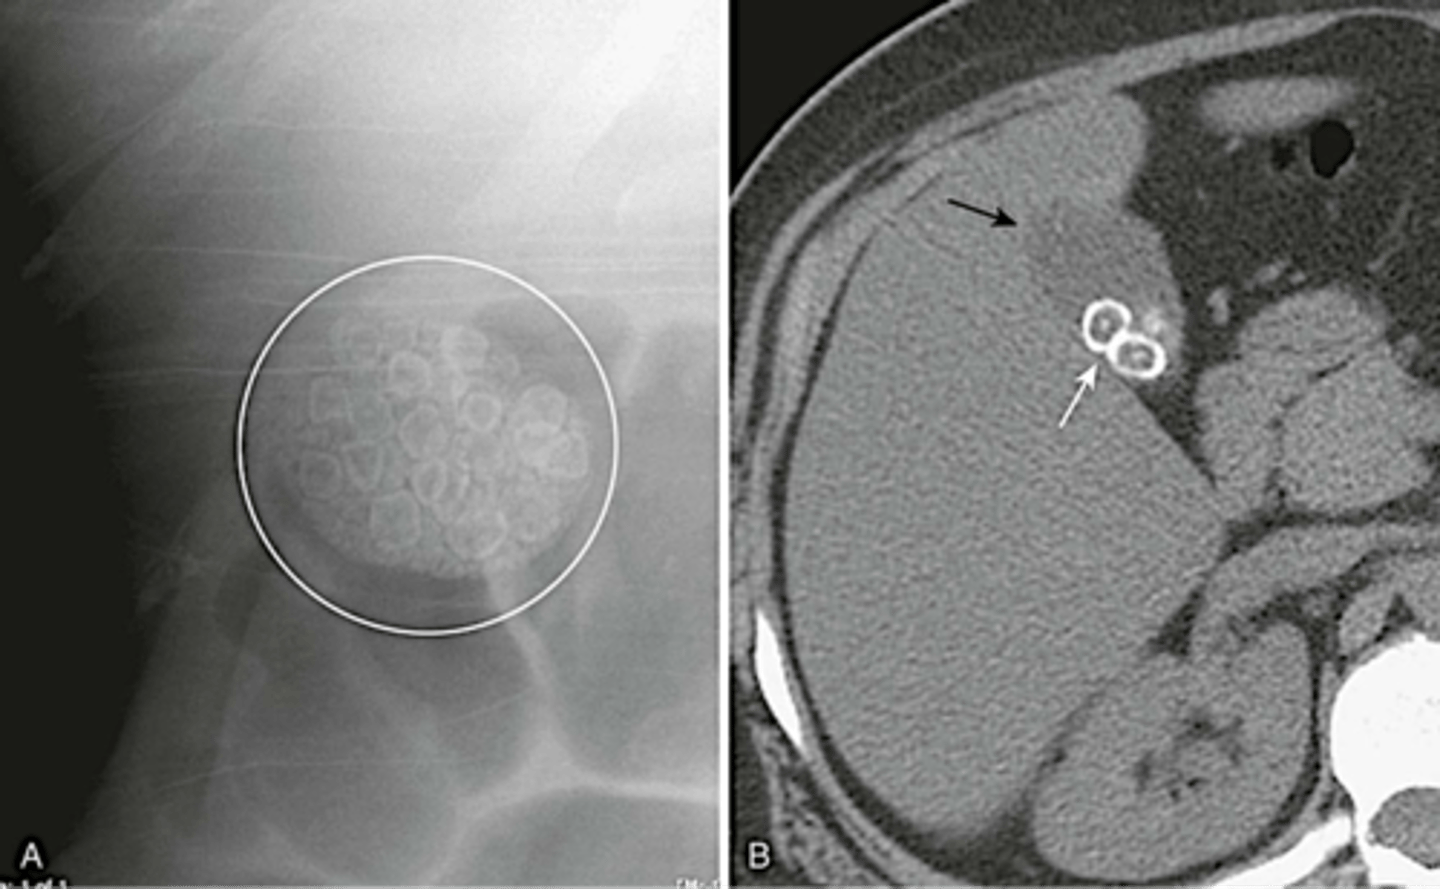

Gallstones (pic 2)

Gallstones (pic 3)

Gallstones (pic 4)